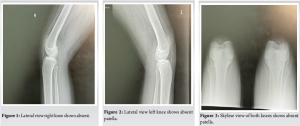

Case Report: We are presenting 35-years-old free medically, active soldier referred to the orthopedic clinic from family medicine after noticing abnormal incidental findings on X-rays. On inquiring him, he doesn’t recall any problem during his childhood and performing his military duties. On clinical examination of the patient, he had characteristic features of patellar absence with prominent femoral condyles and a hollow sulcus.

We are presenting 35-years-old free medically, active soldier referred to the orthopedic clinic from family medicine after noticing abnormal incidental findings on X-rays (Fig. 1-4).

On inquiring him, he doesn’t recall any problem during his childhood and performing his military duties. On clinical examination of the patient, he had characteristic features of patellar absence with prominent femoral condyles and hollow sulcus as per computed tomography (CT) both knees (Fig. 5,6).

He has good quadriceps and hamstring power 5/5. No other abnormalities were detected in his upper and lower limbs. Potential biomechanical adaptations that help to maintain normal gait and joint kinematics in this patient with congenital absence of the patella, specifically mechanisms that prevent knee hyperextension. This may include strengthening or altered recruitment of surrounding musculature (e.g., hamstrings, hip flexors, gastrocnemius), and modified joint alignment or ligament tensioning within normal compare to other studies. Both static postures and dynamic loading scenarios, for example, walking and stair climbing, have been stable movements, which are normally enhance quadriceps efficiency by increasing the moment arm and increased hamstring stress due to compensatory function in absence of the patella (Fig. 5). His blood parameters of liver function test, renal function test, and bone profile and labs are all normal (Table 1). Patient’s hip joints demonstrated a normal range of movement and his ankle joints were also normal. The rest of her musculoskeletal exam was also normal. His cardiovascular, neurological, and abdominal examinations were all normal (Fig. 5). CT chest, abdomen, and pelvis showed no osseous or visceral abnormal. (Fig. 7 & 8).